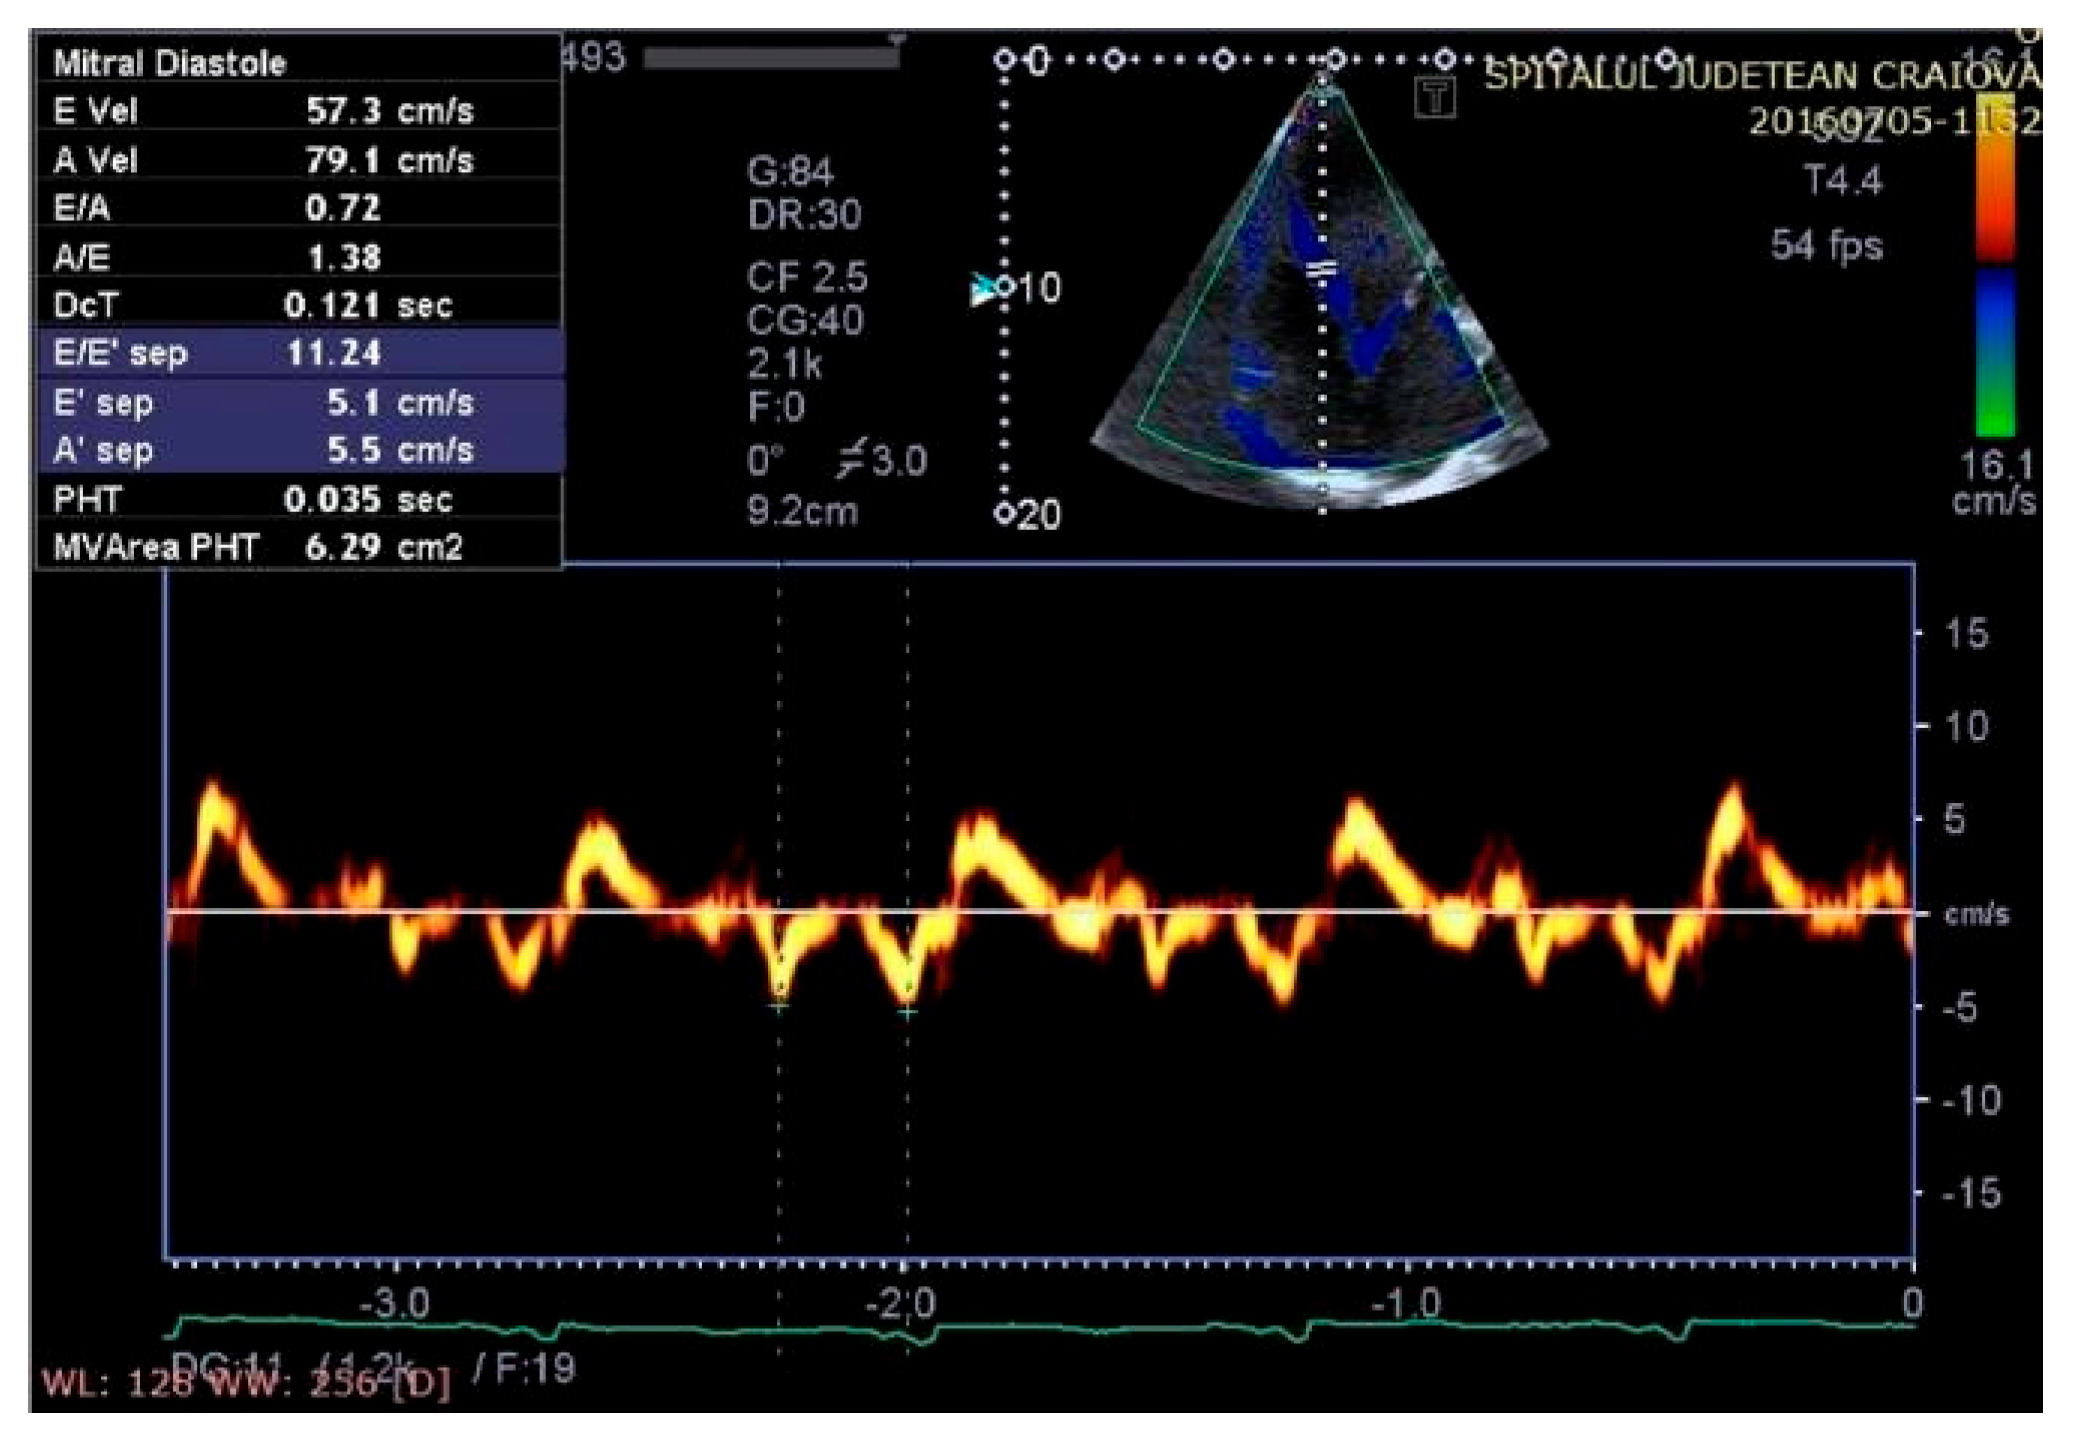

Figure 8.

Aspect of waveforms of tissue Doppler interrogation at the interventricular septum before therapy with a cardiac resynchronization device (yellow color).

Figure 9.

Aspect of waveforms of tissue Doppler interrogation at the interventricular septum after therapy with a cardiac resynchronization device (yellow color).